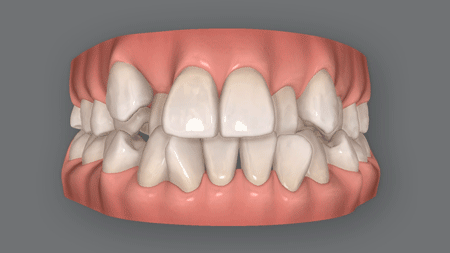

精密検査

治療計画

(クリンチェック)